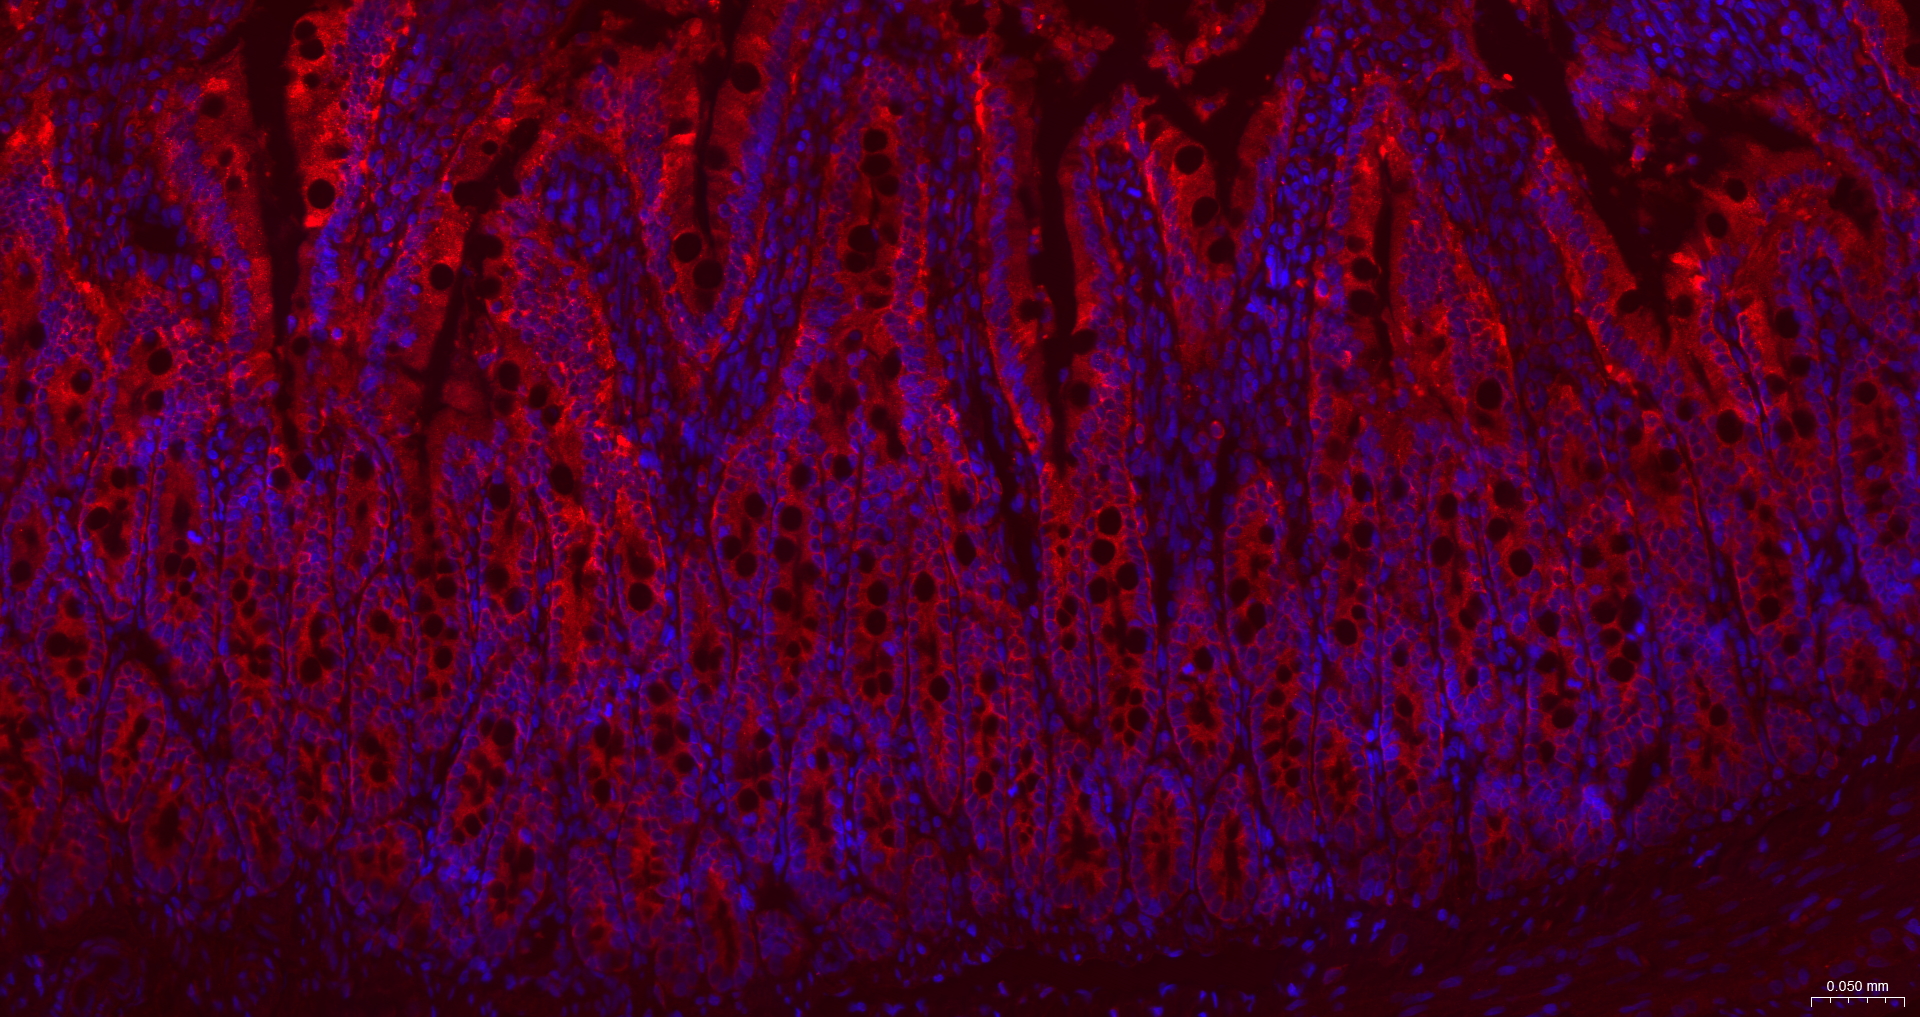

IF(IHC-P) IFIHC-P1:100-500